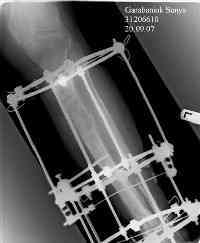

Re: Дефект и остеомиелит tibia